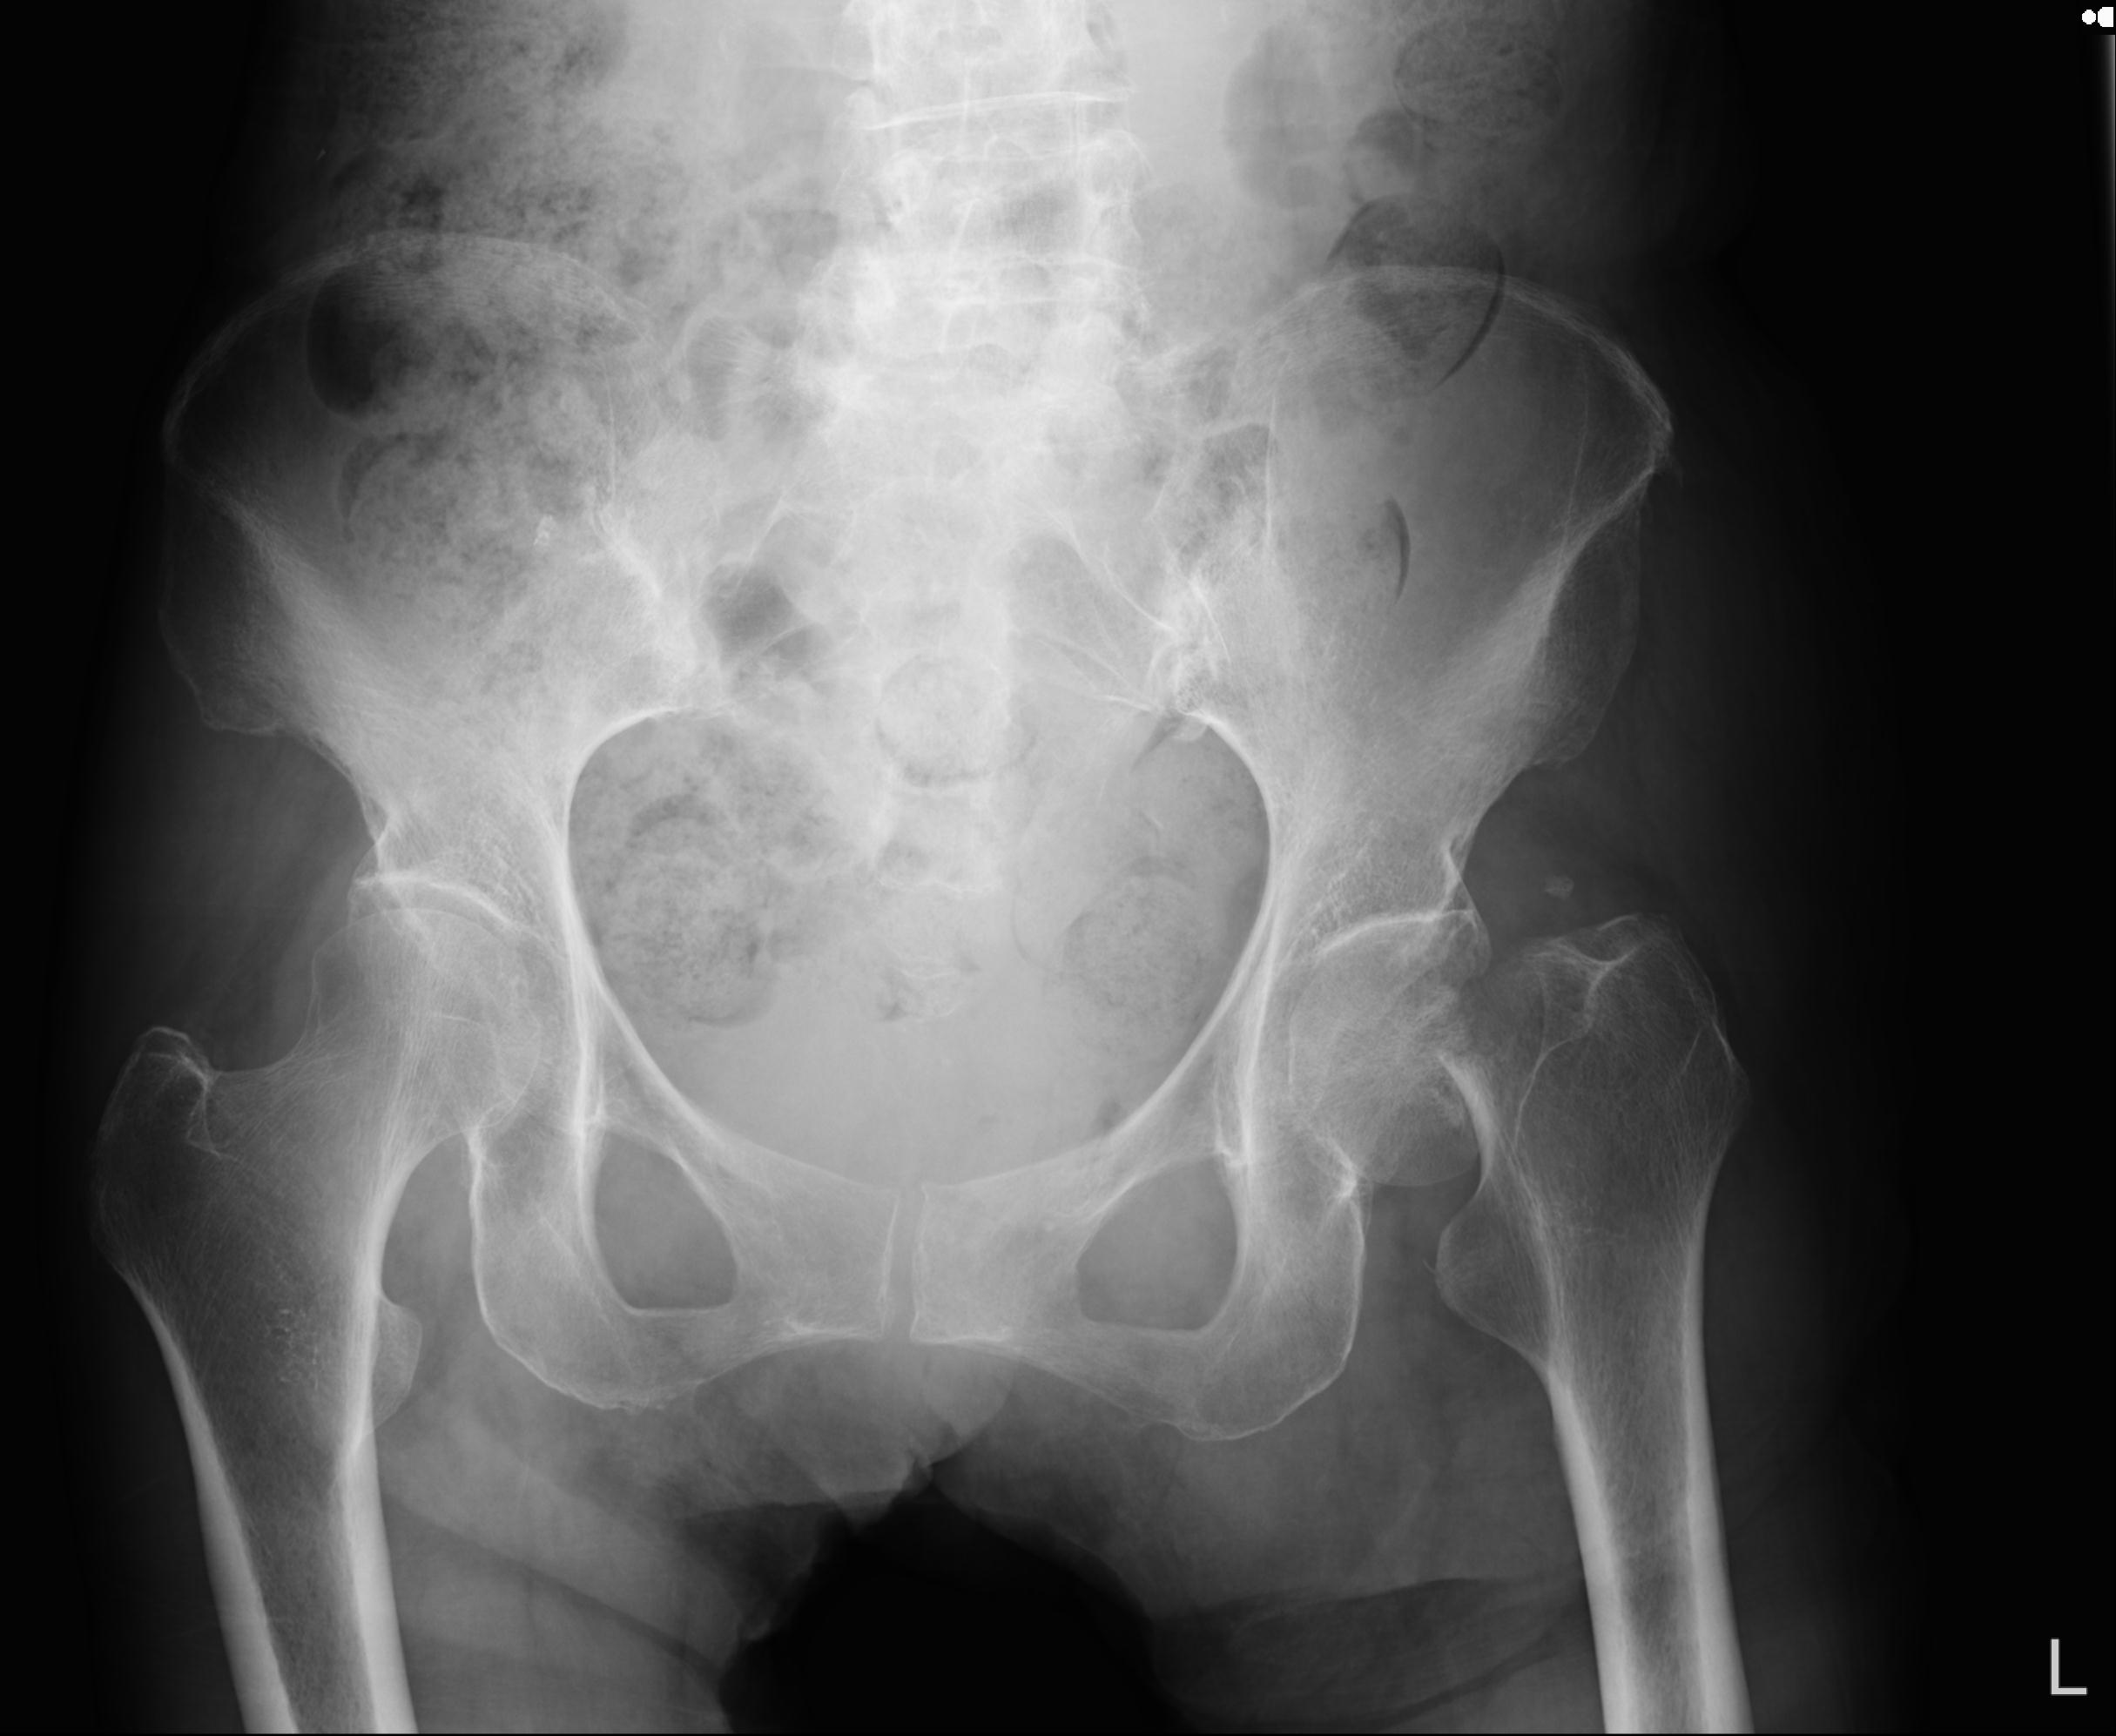

110286 2/17 股関節 2R 74歳女性 右人工骨頭

102903 股関節 2R 1/28 +股関節 2R 1/29 78歳女性 左人工骨頭

100703 1/27 両股正面+軸 1/29 両股正面+軸 94歳女性 パンソンロン

46666 1/28 両股正面+軸と 1/26 右手関節 2R 76歳女性 右転子部骨折

37 1/18 両股正面+軸 1/22 2R 86歳女性 右転子下

82084 1/14 1/20 股関節 2R 78歳男性 右人工骨頭

91569 3/25 両股正面とラウエン 70歳女性 人工骨頭+バンクーバー